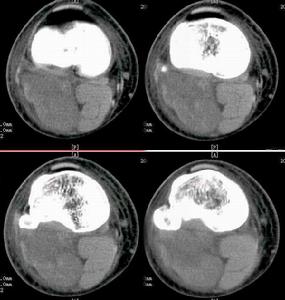

何杰金氏淋巴瘤CT圖HD的國際臨床分期(AnnArbor會議,1971)標準如下。